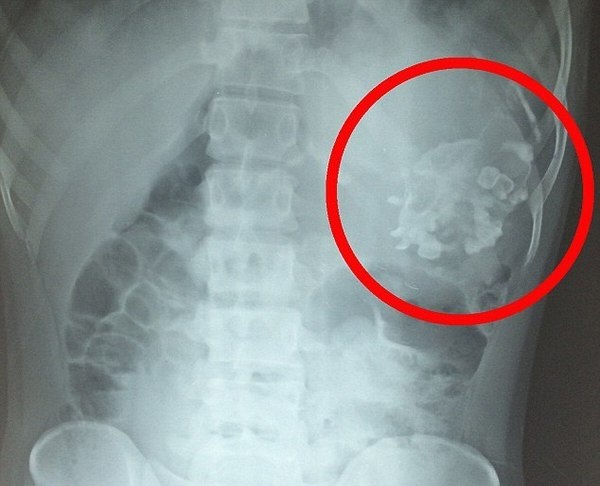

21-летний Нарендра Кумар с детства страдал всевозможными недомоганиями, включая потерю веса.

Причиной  оказался близнец-паразит с зубами и волосами, прятавшийся внутри молодого человека. Молодой человек был успешно прооперирован.

1. Плод находится в другом целиком. (Второй эмбрион расположен либо в брюшной полости, либо в грудной клетке «носителя». Реже всего плод поселяется в голове «носителя».)